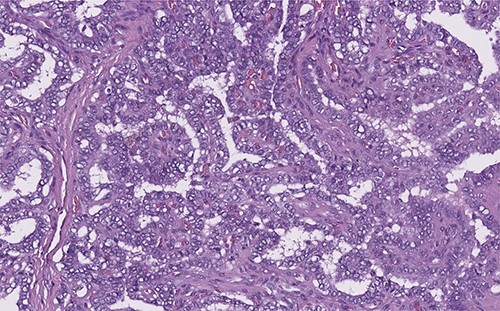

Two months ago, the patient began with a volume increasing mass in the anterior side of the neck, without any added symptoms. The patient visited a physician who asked for a thyroid ultrasound, which was performed on august 16th of the present year. The study showed a midline-neck heterogeneous cystic mass. The follow-up plan included a contrast-enhanced computer tomography scan, to analyze the possibility of a neo proliferative mass, as the radiology specialist suggested. The scan was performed 2 days later, and it revealed a solid cystic tumor, with multiple septa, localized on the midline adjacent to the thyroid gland and its pyramidal lobe (Fig. 5). The histopathology report suggested a thyroglossal duct cyst related to a papillary-type thyroid cancer (Fig. 6).

Papillary thyroid carcinoma: true papillae with multiple branching, stromal stalk with microvessels (left). Note the optically clear (empty, ground-glass) nuclei with thick nuclear membrane (H&E, high power).